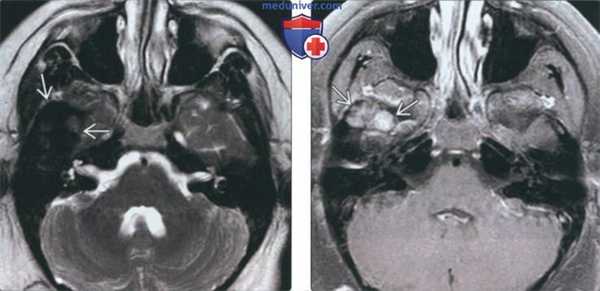

(Слева) На аксиальной МРТ (Т2 ВИ) на уровне дна средней черепной ямки над областью правого ВНЧС визуализируется объемное образование с сигналом очень низкой интенсивности обусловленное распространением пигментного ворсинчато-узлового синовита из ВНЧС в полость черепа.

(Справа) На аксиальной МРТ (Т1 ВИ C+FS) у этого же пациента определяется легкое контрастное усиление солидных участков объемного образования у пациента с пигментным ворсинчато-узловым синовитом.

(Слева) При MPT T1BИ FS с КУ в аксиальной проекции, выполненной пациенту с пигментным ворсинчато-узелковым синовитом (ПВУС), в расширенном суставном пространстве правого ВНЧС и вокруг него визуализируются многочисленные узлы с гипоинтенсивным сигналом. Обратите внимание, что контрстаное усиление выражено минимально.

(Справа) При корональной МРТ в режиме STIR у пациента, страдающего ПВУС, вокруг головки мыщелка нижней челюсти справа визуализируются узлы с гипоинтенсивным сигналом. Обратите внимание на «засвечивание» (блюминг-артефакт) основания черепа, обусловленное включением гемосидерина в узлах, и являющееся практически патогномоничным признаком.